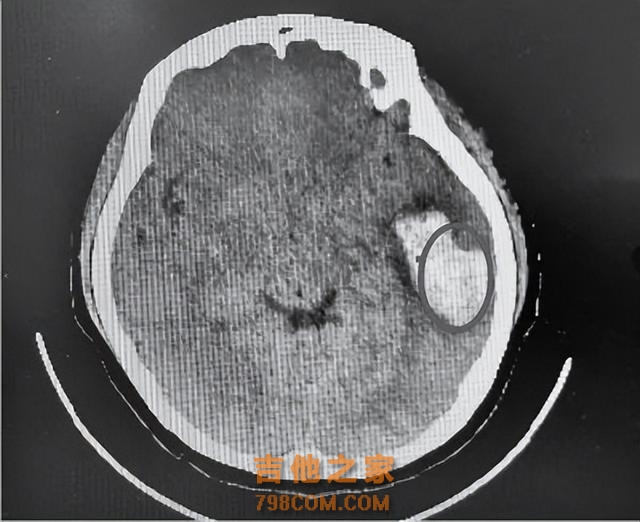

知名歌手在演唱会现场倒下,已确认去世!医生紧急提醒

患者的脑部检查结果,圆圈处为出血区域

“出血量比较大,有近30毫升。如果未及时就医,后果不堪设想。” 副主任医师刘奇说,欢欢虽然年纪比较小,症状表现比较轻,但也不能大意。